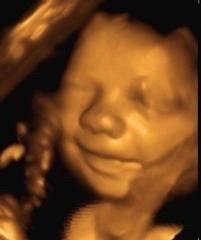

Little Angels 3D/4D Ultrasound Imaging in McDonough, GA, offers advanced ultrasound services that combine state-of-the-art technology with customer-focused care. Their dedicated team of licensed sonographers and radiologists provides both in-studio and mobile ultrasound experiences, ensuring families can witness important milestones with stunning 3D, 4D, and HD 5D imaging.

Beyond elective fetal ultrasounds, Little Angels offers a comprehensive range of diagnostic imaging services for various medical conditions, delivered in a warm and welcoming environment. Clients can expect high-quality ultrasound imaging complemented by luxurious amenities, creating a memorable bonding experience with their unborn children.